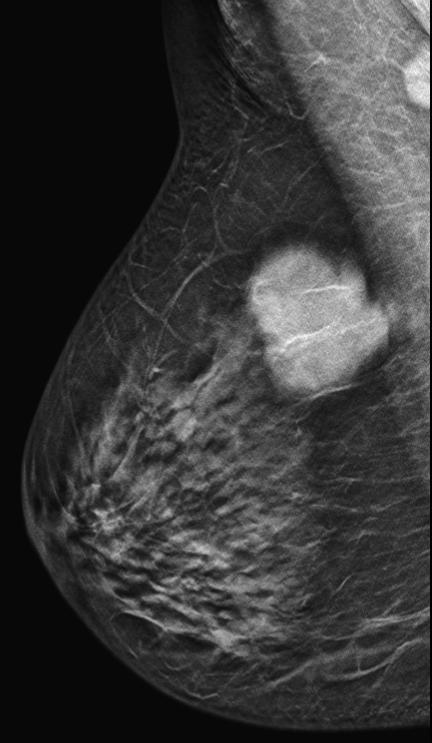

Bilateral digital mammography with tomosynthesis and ultrasonography was done. Mammography revealed a high-density irregular mass with multilobulated margins in the upper and outer quadrant of the left breast. The mass was located eccentric to the nipple. No associated calcifications were seen.No axillary lymphadenopathy. Ultrasonography revealed a hypoechoic irregular mass with multilobulated margins at 2 o clock position in the left breast. Color doppler revealed minimal peripheral vascularity. Arfi elastography revealed the mass to be hard. A BI-RADS assessment category of 4C was given with a recommendation for a core needle biopsy. Histopathology Invasive ductal carcinoma .IHC -ER 95 %,PR-95% ,HER 2 -Negative and KI -67-20%. PET CT revealed an FDG avid lesion in the upper outer quadrant of the left breast with no axillary or distant metastases.